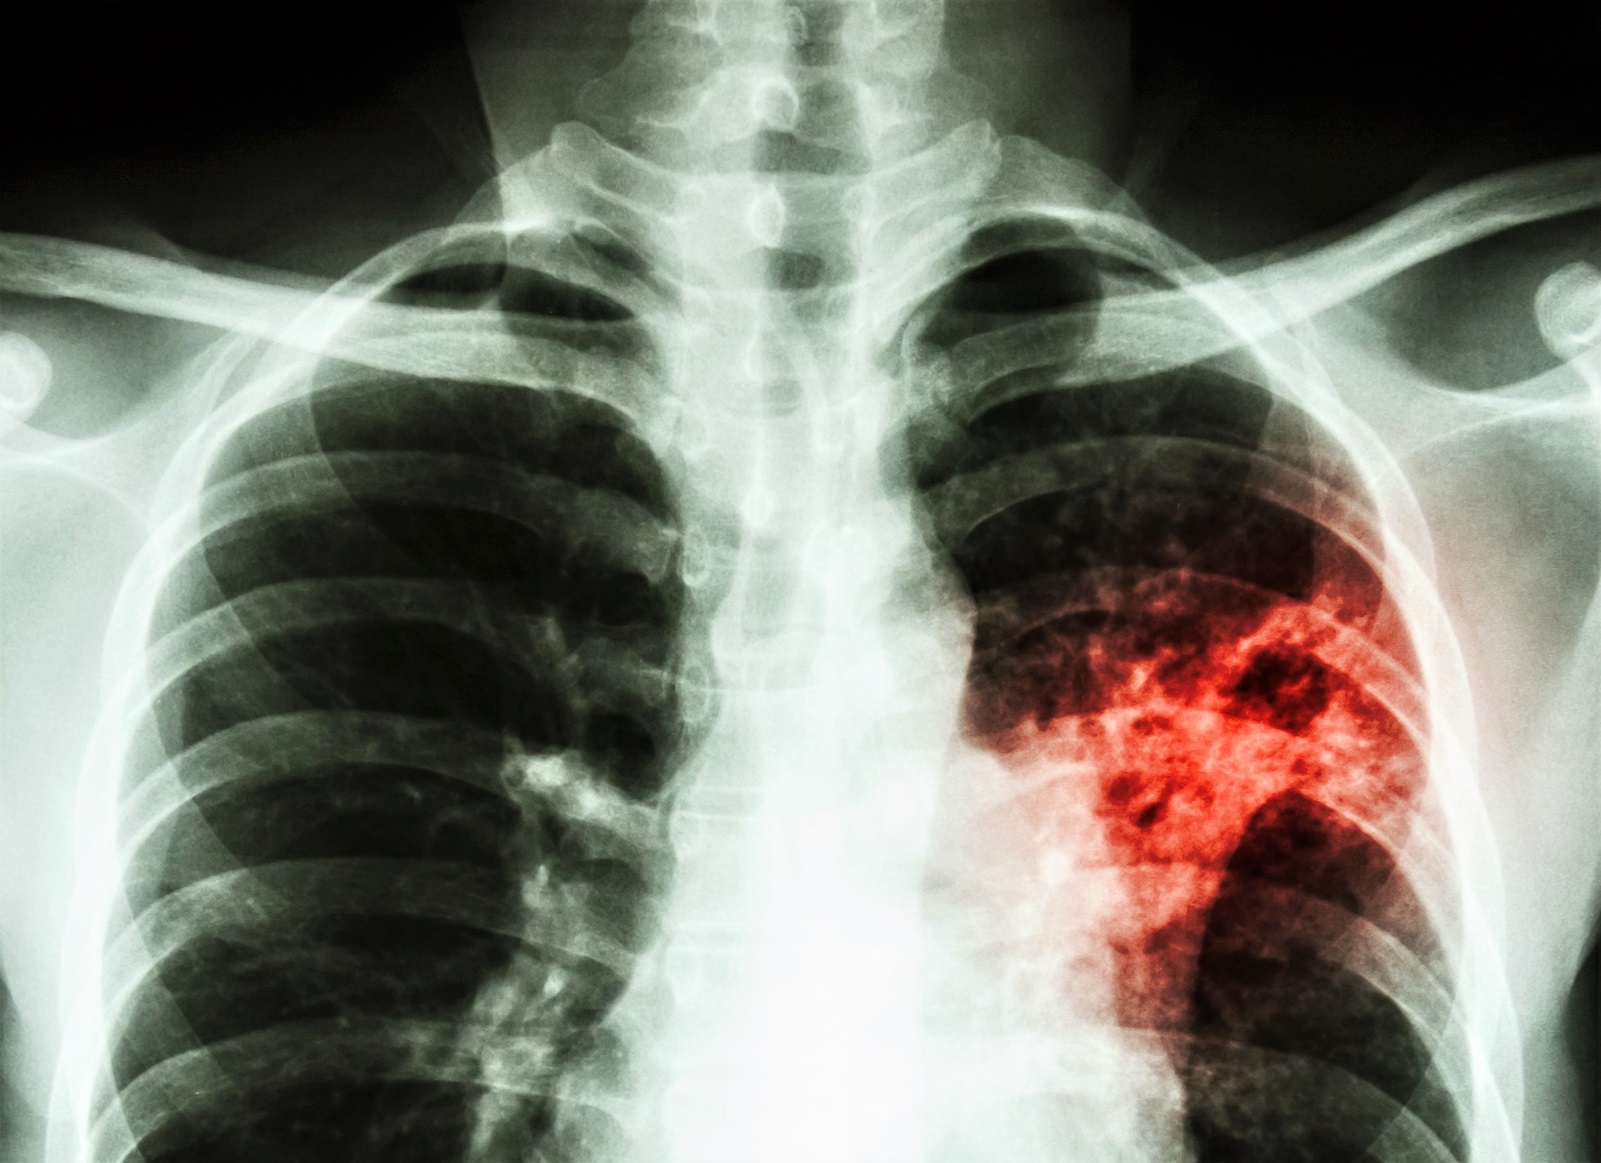

Die Erkrankung wird durch verschiedene Arten von Mykobakterien verursacht und befällt beim Menschen als Lungentuberkulose am häufigsten die Lunge bei Immundefekt zeigt sich vermehrt auch ein Befall außerhalb der Lunge. Die Erreger können aber auch andere Organe wie den Darm oder die Knochen befallen. Santé publique France publie les données annuelles de surveillance de la tuberculose en France.

Tuberkulose wird durch Bakterien ausgelöstDie Erreger befallen überwiegend die Lunge und lösen als erstes Zeichen unter anderem Husten aus können aber auch fast jedes andere Organ betreffen und schwere Erkrankungen auslösen. Leoniesrleonie Rose Fält-hansenroseflthansen Dr. Tuberculose en France.

It is spread through the air when a person with TB disease of the lungs or throat coughs speaks or sings and people nearby breathe in these bacteria and become infected. It mainly affects the lungs but it can affect any part of the body including the tummy abdomen glands bones and nervous system. Daher betrifft Tuberkulose in den meisten Fällen zuerst die Lunge.